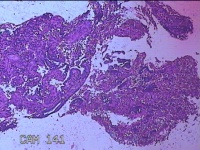

性别

女

年龄

46岁

临床诊断

异常子宫出血

一般病史

阴道流血伴血块6天。

标本名称

宫腔内组织

大体所见

灰白暗红色不规则碎组织2.5x2x0.7cm一堆。

图1